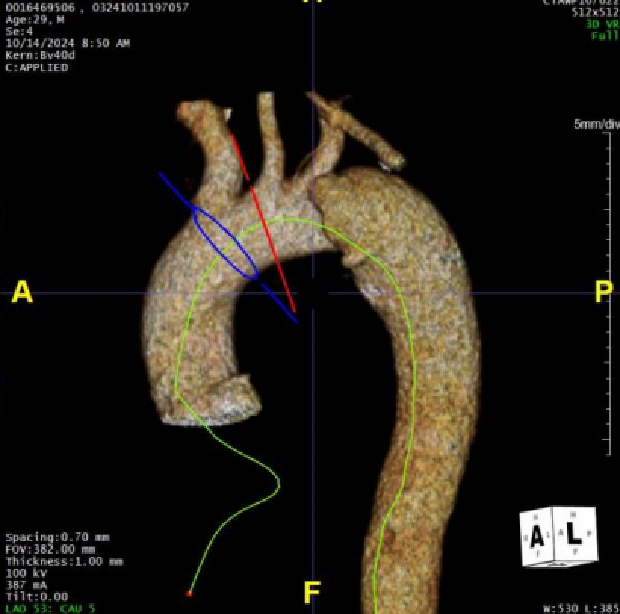

★病例1

28岁男性,急性复杂型B型AD,急诊TEVAR治疗